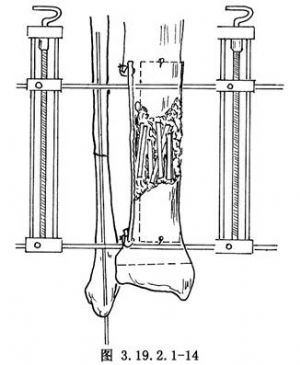

11.5 5.內固定

若脛骨遠端較長,可於脛骨遠端骺板上方1.25~2cm處和脛骨近側段橫行穿入斯氏針,用Charnley加壓器固定,保持脛骨兩斷端牢固嵌壓和良好對位(圖3.19.2.1-14)。若脛骨遠端短小,可用較粗的斯氏釘逆行法髓內固定脛骨。先從脛骨遠斷端向遠側打入斯氏釘,穿過脛骨遠端骨骺中心、踝關節、距下關節,從跟骨蹠面穿出,然後對正脛骨遠、近端,將斯氏釘打進脛骨近端,其理想的穿釘方向應使釘的近端恰在脛骨後側皮質。遠側釘尖埋於皮下(圖3.19.2.1-15)。